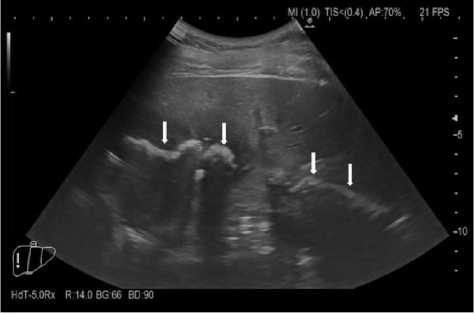

По результатам проведённого УЗИ органов брюшной полости (конвексным датчиком) в правом подпечёночном пространстве визуализировано гиперэхогенное образование с эффектом массивной акустической тени. Описанное образование линейной формы, с неровным контуром протяжённостью до 80 мм, в каудальной части образование с округлыми (кольцевидными) контурами. В краниальном отделе образование тесно прилежит к диафрагме (рис. 1, 2). Правый купол диафрагмы локально утолщён от 17 до 24 мм, контур диафрагмы на участке до 15 мм прослежен нечётко. В правой плевральной полости на фоне гиповентиляции лёгочной ткани и инфильтративных изменений купола диафрагмы определено отграниченное жидкостное скопление с неоднородным содержимым, размерами до 38×40×45 мм. Желчный пузырь удалён. Стенки холедоха не утолщены, конкрементов нет, просвет – 4 мм.

Заключение: УЗ-признаки очагового образования подпечёночного пространства, инфильтративные изменения правого купола диафрагмы (с подозрением на свищ) (рис. 3), отграниченного жидкостного скопления в правой плевральной полости, состояние после холецистэктомии.

Рисунок 3. Ультразвуковое исследование в В-режиме: 1 – ре берно-диафрагмальный синус (отмечено курсором); 2 – ткань нижней доли правого легкого с признаками гиповентиляции; 3 – паренхима печени; 4 – отграниченное жидкостное скопление с неоднородным содержимым в правой плевральной полости Figure 3. B-mode ultrasound: 1 – costophrenic sinus (marked with a cursor); 2 – tissue of the lower lobe of the right lung with signs of hypoventilation; 3 – liver parenchyma; 4 – limited fluid accumulation with hetergeneous contents in the right pleural cavity